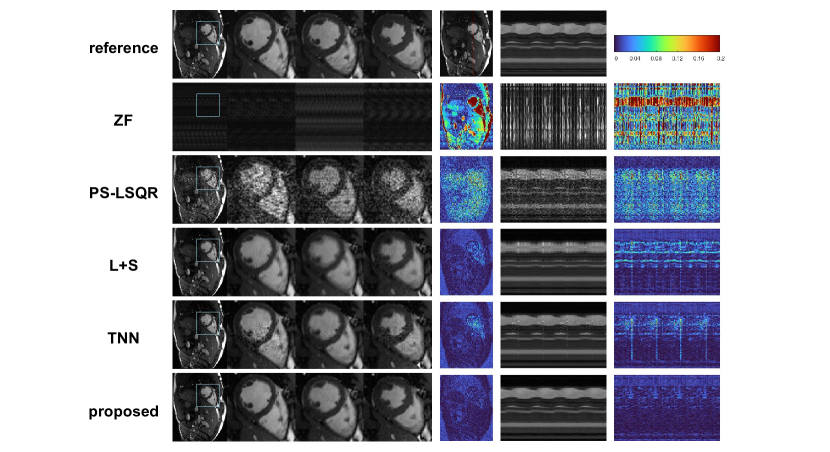

5.4 Comparative Experiments with non-PS model Methods

The comparison of the reconstructed images with the non-PS model methods is shown in Figure 10. Because the undersampling rate is very high (), the images reconstructed by ZF algorithm have almost no meaningful structures. The images reconstructed by PS-LSQR method are severely corrupted by noise. The L+S method has good denoising effect. The images reconstructed by the L+S method have much better visual quality than PS-LSQR method. However, significant over-smoothing effect can be perceived from the images reconstructed by the L+S method. The loss of image details is most obvious at the frame of cardiac contraction, where the blood-myocardium boundary is obscured. The images reconstructed by the TNN method are sharper. Compared with the L+S method, the reconstructed motion profile of the TNN method is more consistent with the reference. However, noise corruption has not been removed clearly for the TNN method. Residual noise-like artefacts can be observed on the zoomed images and M-mode images. The image quality of the proposed accelerated PS model method outperforms other methods significantly. The quantitative metrics of this study are listed in Table 2, which are consistent with the visual appearance.